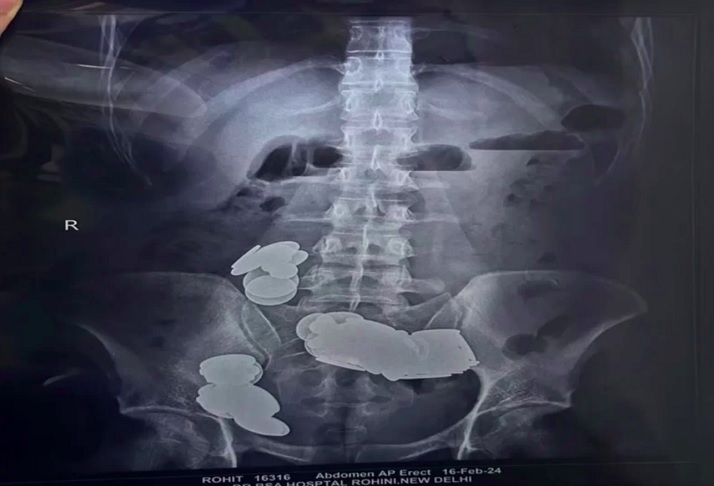

À beira da morte: Homem engole 39 moedas e 37 ímãs para ‘auxiliar na musculação’